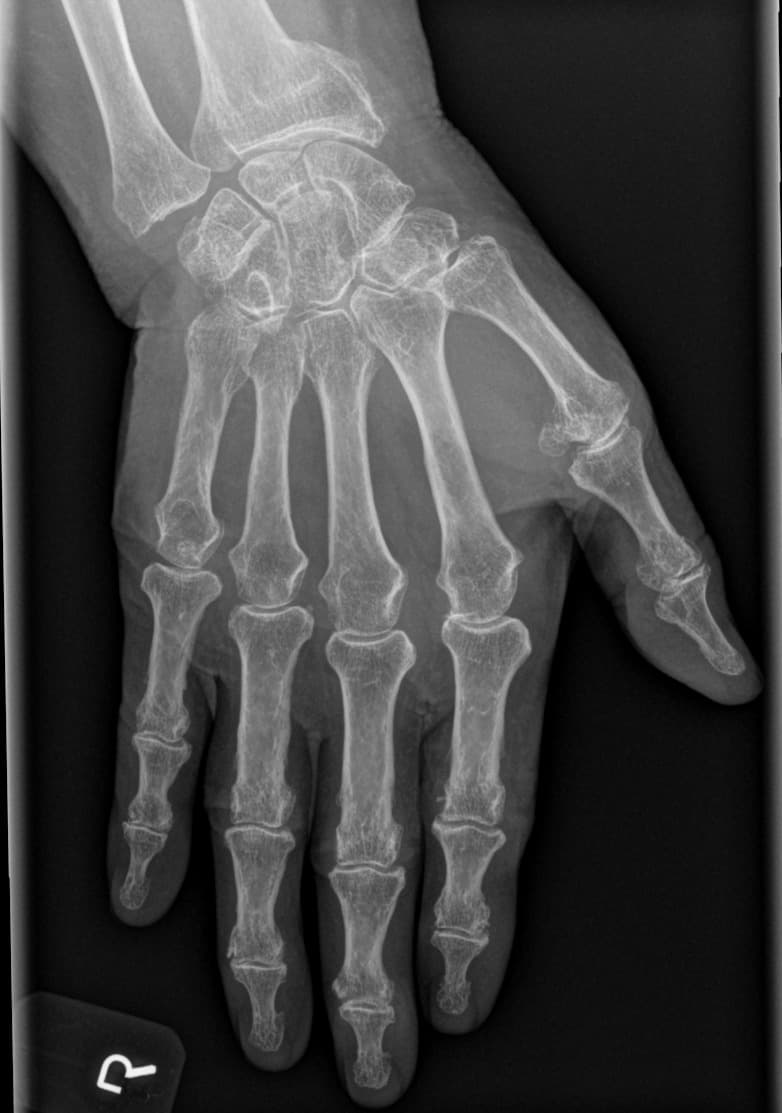

Røde flag i røntgen ved alignment og fraktur-opfølgning

Røntgenvurdering i opfølgning bør ikke kun være beskrivende; den bør tydeligt sammenligne alignment, helingstendens og eventuel progression af deformitet.